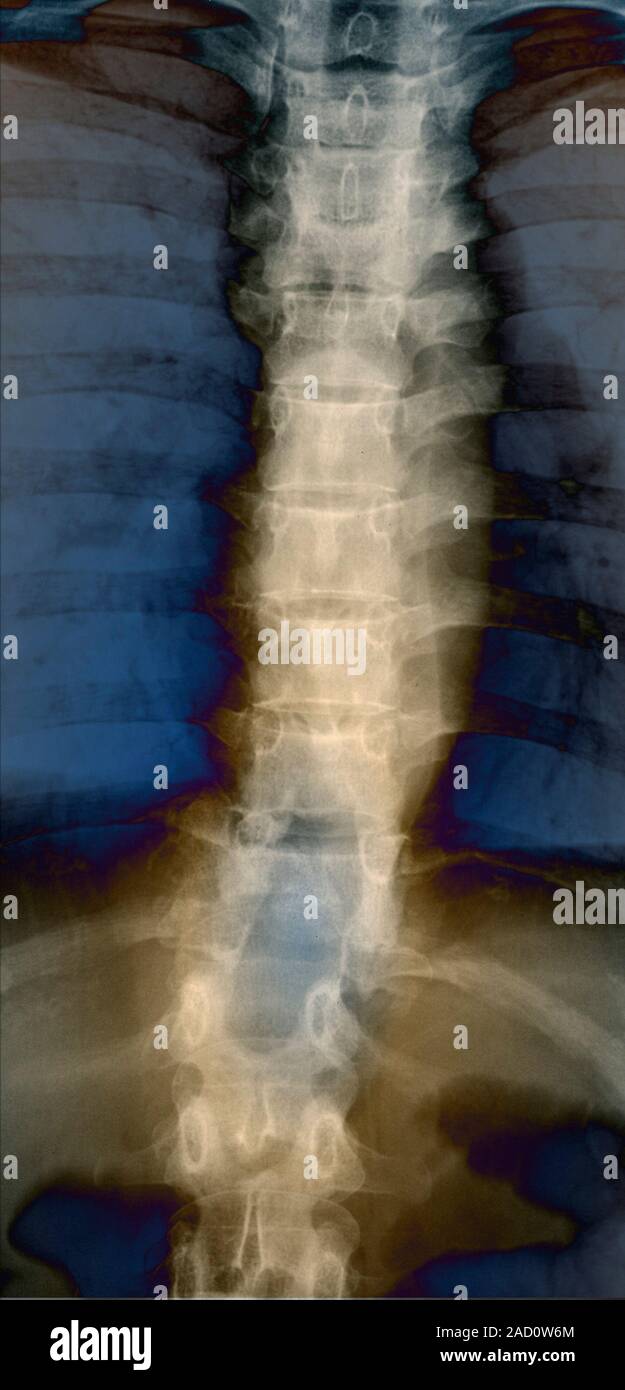

Spine in Pott's disease. Xray of a section through the spine of a 22 Pott's Disease Back Pott disease is tuberculosis of the spine that occurs usually due to hematogenous spread from other sites, often the lungs. Pott's disease is also known as tuberculosis spondylitis or spinal tuberculosis. Tuberculous spondylitis, also known as pott disease, refers to vertebral body osteomyelitis and intervertebral discitis from tuberculosis (tb). Back pain in tuberculosis can be related to the active disease. Pott's Disease Back.

Pott's disease. Coloured Xray of the spine of a patient with Pott's Pott's Disease Back Back pain in tuberculosis can be related to the active disease itself (secondary to inflammation), bone destruction and instability. Pott's disease is also known as tuberculosis spondylitis or spinal tuberculosis. Pott disease is tuberculosis of the spine that occurs usually due to hematogenous spread from other sites, often the lungs. Rest pain is pathognomonic, and rarely,. Tuberculous spondylitis, also known. Pott's Disease Back.